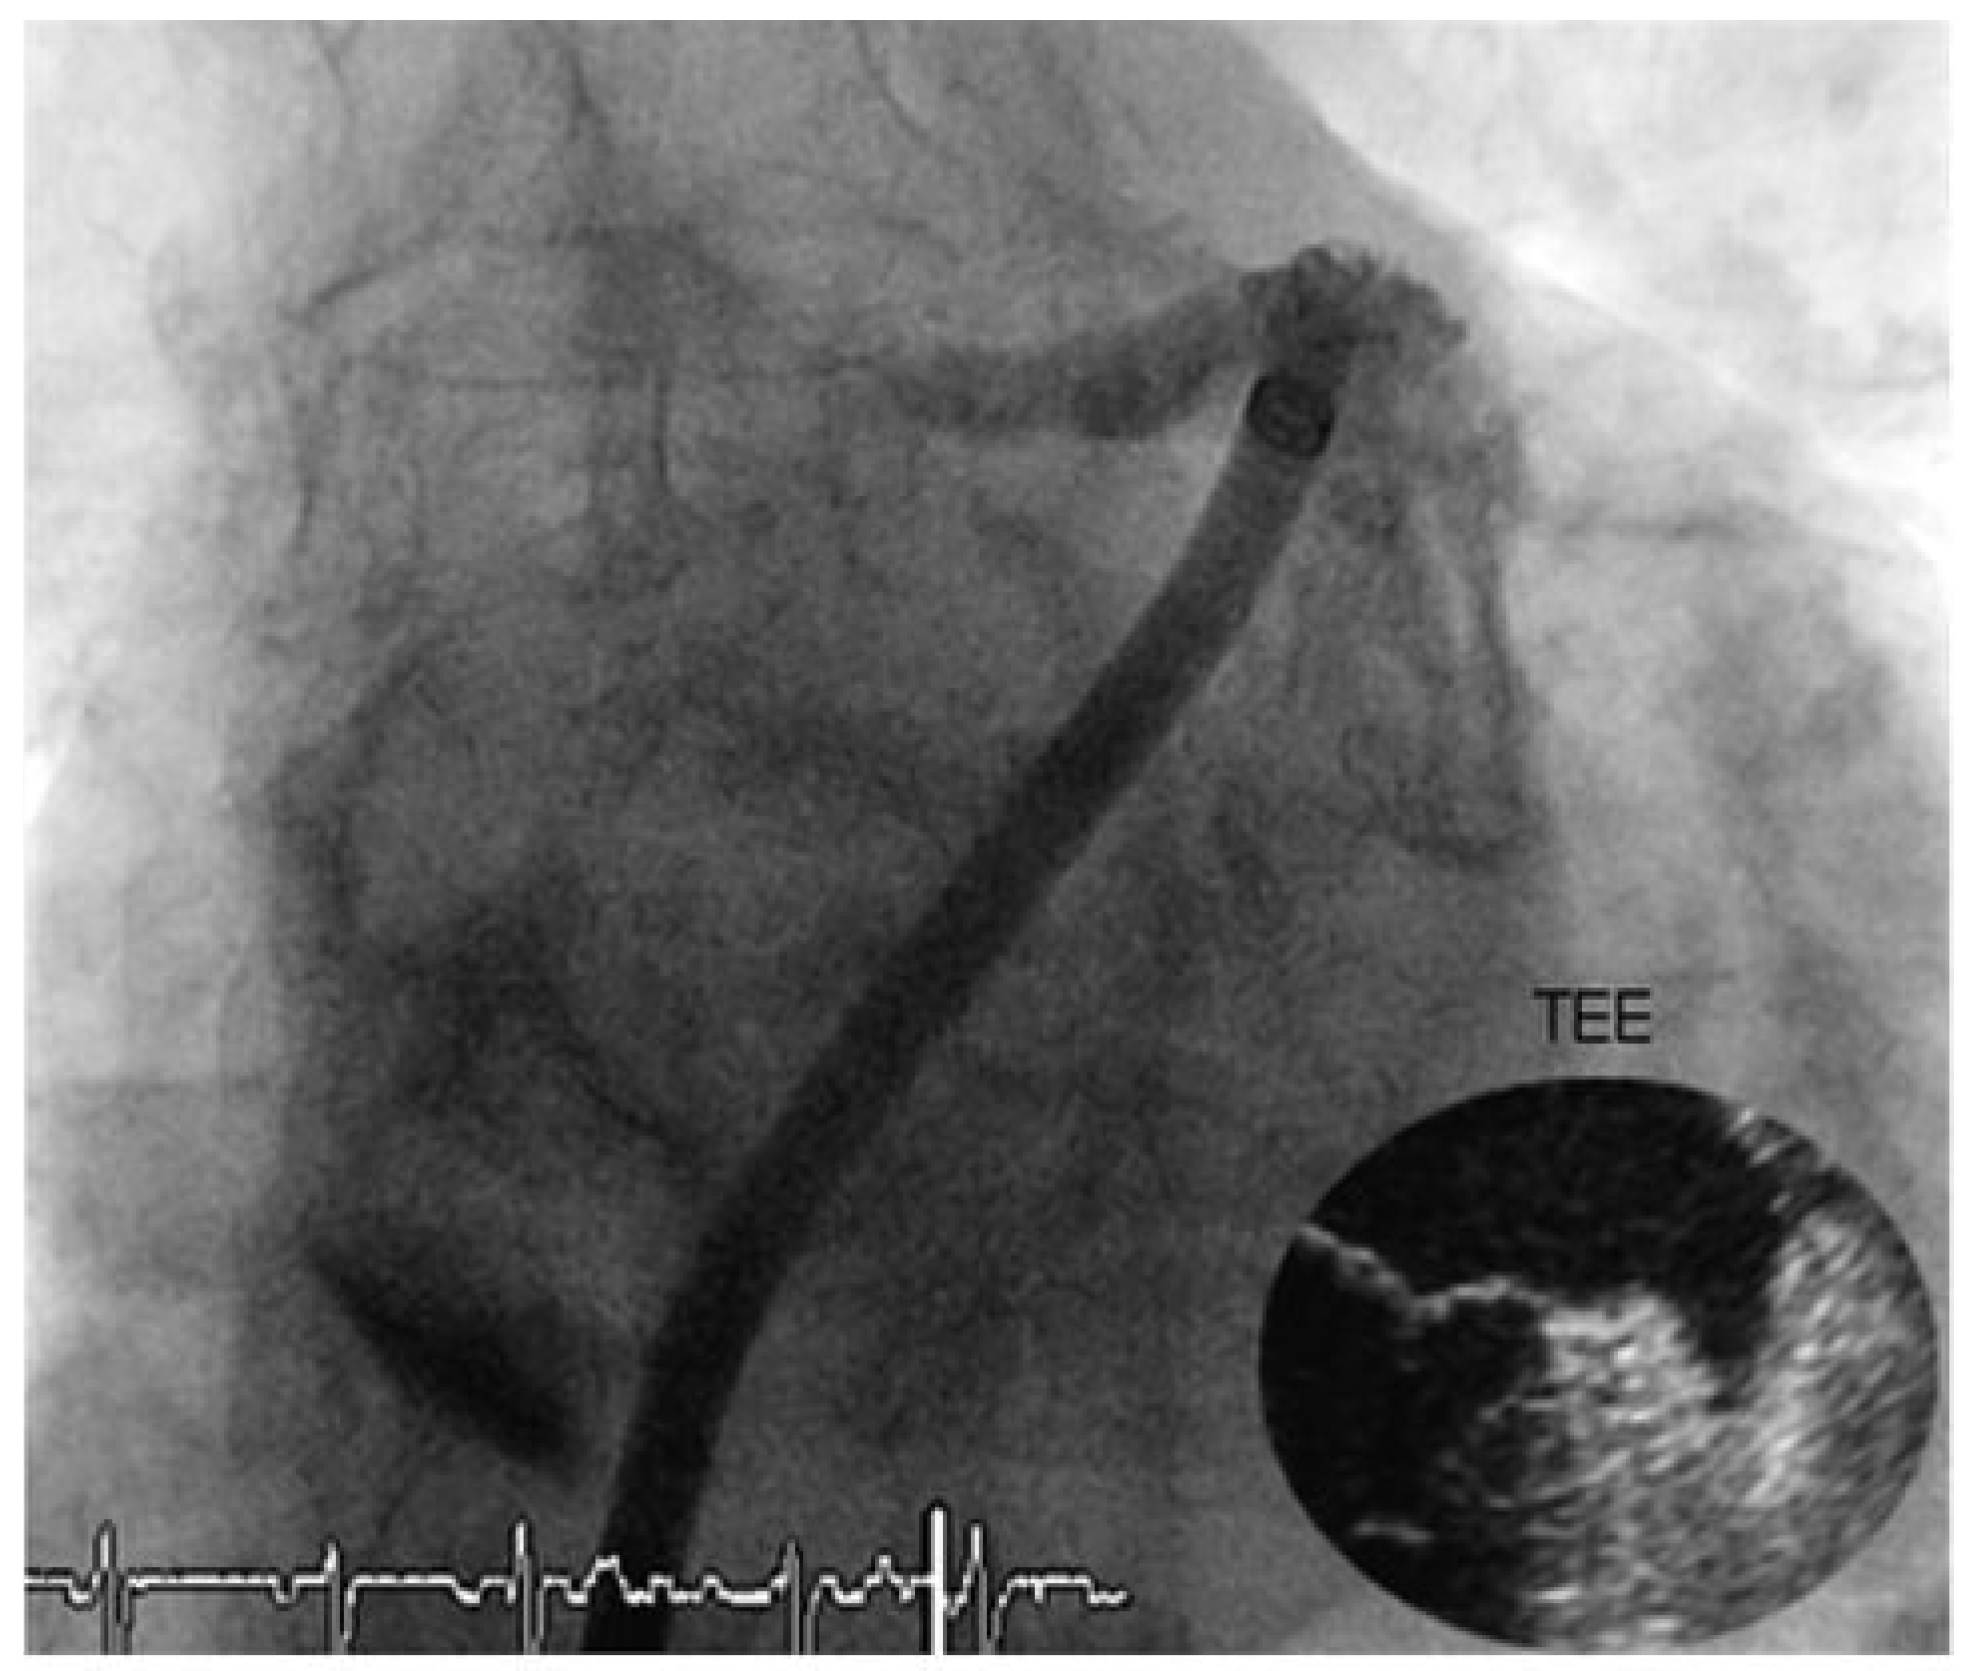

Through a transfemoral venous approach and transseptal puncture, the left atrial appendage was identified and an Amplatzer cardiac Plug 20 mm was positioned in the entry of the appendage. A stable position of the device and complete occlusion of the retroverted, single-lobulated appendage were verified by angiography before the device was released from the catheter (

Figure 1 and

Figure 2). Thereafter, coronary angiography was performed which showed significant stenosis of the mid left anterior descending coronary artery (LAD) and the proximal left circumflex coronary artery (LCX). Following successful treatment with two everolimus-eluting stents, respectively (